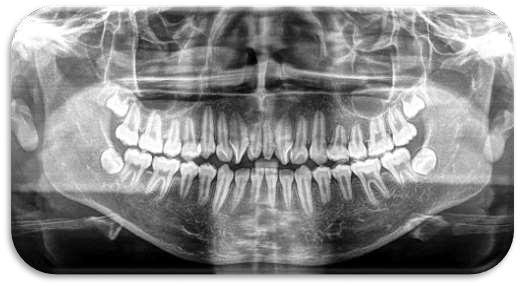

FRACTURA DE LOS MAXILARES

Las fracturas maxilares representan un desafío diagnóstico y terapéutico, ya que afectan a estructuras dentarias, óseas y senos paranasales.

La tomografía computada de haz cónico (CBCT) es el método de elección para valorar con precisión la extensión y ubicación de las fracturas debido a su capacidad de mostrar estructuras en tres dimensiones con alta definición y con diferentes filtros para una visibilidad adecuada a cada estructura

Desarrollo

En este caso se presenta una fractura maxilar y avulsión de pieza 1 1, la fractura de cortical vestibular va desde pieza 1 2 hasta 1 5 asociada a múltiples fracturas en cortical ósea vestibular de seno maxilar derecho. Enfatizando la importancia del diagnóstico tomográfico para este tipo de situaciones cuyo aporte en este caso particular es de alto valor diagnóstico.

Conclusión

La tomografía computada de haz cónico (CBCT) es indispensable para la evaluación de fracturas maxilofaciales complejas.

Las fracturas de los maxilares con compromiso de seno maxilar requieren de un diagnóstico oportuno para evitar complicaciones previas y durante la terapéutica

El abordaje terapéutico debe ser multidisciplinario y personalizado según las características individuales de cada caso, valorando la extensión de la lesión y el estado de las piezas dentarias afectadas.